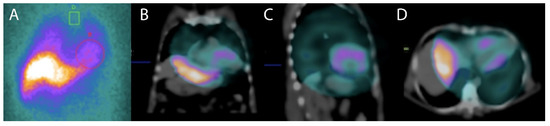

- Miranda, C.H.; Figueiredo, A.B.; Maciel, B.C.; Marin-Neto, J.A.; Simoes, M.V. Sustained ventricular tachycardia is associated with regional myocardial sympathetic denervation assessed with 123I-metaiodobenzylguanidine in chronic Chagas cardiomyopathy. J. Nucl. Med. 2011, 52, 504–510. [Google Scholar] [CrossRef]

- Gadioli, L.P.; Miranda, C.H.; Pintya, A.O.; de Figueiredo, A.B.; Schmidt, A.; Maciel, B.C.; Marin-Neto, J.A.; Simoes, M.V. The severity of ventricular arrhythmia correlates with the extent of myocardial sympathetic denervation, but not with myocardial fibrosis extent in chronic Chagas cardiomyopathy: Chagas disease, denervation and arrhythmia. J. Nucl. Cardiol. 2018, 25, 75–83. [Google Scholar] [CrossRef]

- Garg, G.; Cohen, S.; Neches, R.; Travin, M.I. Cardiac (18)F-FDG uptake in chagas disease. J. Nucl. Cardiol. 2016, 23, 321–325. [Google Scholar] [CrossRef]

- Shapiro, H.; Meymandi, S.; Shivkumar, K.; Bradfield, J.S. Cardiac inflammation and ventricular tachycardia in Chagas disease. HeartRhythm Case Rep. 2017, 3, 392–395. [Google Scholar] [CrossRef] [PubMed]

- Moll-Bernardes, R.J.; de Oliveira, R.S.; de Brito, A.S.X.; de Almeida, S.A.; Rosado-de-Castro, P.H.; de Sousa, A.S. Can PET/CT be useful in predicting ventricular arrhythmias in Chagas Disease? J. Nucl. Cardiol. 2020, 1–4. [Google Scholar] [CrossRef] [PubMed]